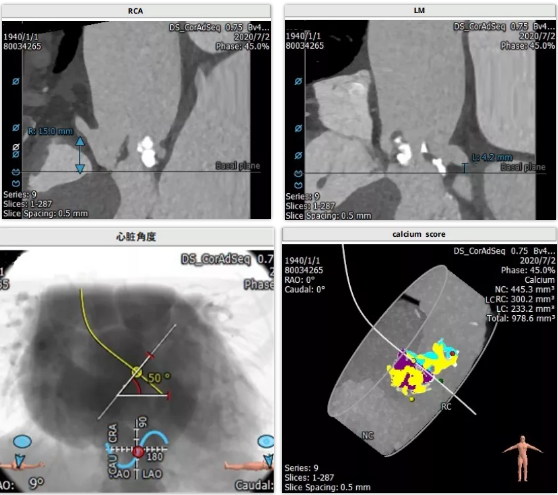

主动脉根部解剖

三叶瓣,重度钙化,左冠开口位置低4.2mm,右冠开口较高15.0mm。法式窦结构大小可,左心室大小尚可,心肌肥厚,升主动脉未见明显扩张,股动脉直径均可。

三叶瓣,重度钙化。左冠 4.2mm 右冠 15mm, sinus:29mm。此病例难点在左冠开口很低,仅4.2mm,窦的结构不大,瓣叶较为冗长。该患者左冠开口低,冠脉堵闭风险高。拟予术中进行左冠保护,20mm球囊扩张,左冠切线位观察瓣叶和冠脉开口相对关系。选择VenusA-Valve L23瓣膜植入。

众所周知,冠状动脉阻塞是TAVI少见却是致命性的并发症,也是术前影像学筛选重点以及患者被排除行TAVI主要原因之一。TAVI冠状动脉阻塞的主要机制是自体瓣膜上翻堵住冠状动脉开口。此外,瓣膜支架放置过高,裙边挡住冠状动脉开口, 也可致冠状动脉阻塞。一旦发生需立即建立体外循环,转开胸开通堵闭冠脉,如抢救不及时,往往会危及生命。因此TAVI术前CT评估认为冠状动脉开口的高度大于10mm,冠脉堵塞不容易发生。如果冠状动脉开口低于10mm,则属于冠状动脉堵塞的高危因素之一,此时要求手术医师结合患者瓦氏窦的大小、瓣叶的形态及瓣叶钙化的情况综合考虑冠状动脉堵塞的风险高低。